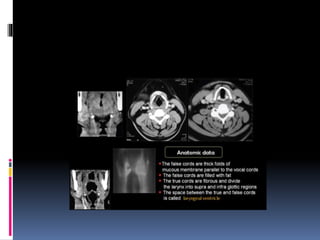

IMAGING OF THE PHARYNX

IMAGING OF LARYNX